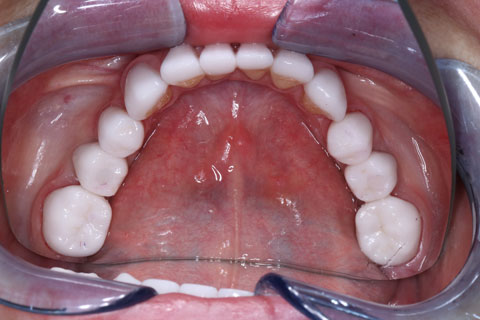

Женщина. 52 года.

Обратилась с жалобами на разрушение зубов 3.6, 4.6, дефекты и дисколорит ранее наложенных пломб. В анамнезе врожденная адентия 1.5, 2.5, 3.5, 4.5

Удалены корни 3.6, 4.6, с одномоментной установкой имплантатов 3.6, 4.6 и забором соединительно-тканного трансплантата с небной поверхности в области 1.6.

Проведена ортопедическая реабилитация.

Фронтальная группа зубов верхней и нижней челюстей – установлены виниры из литий дисиликата.

Жевательная группа – восстановлена коронками из диоксида циркония, в том числе 3.6, 4.6 – коронки на имплантатах.